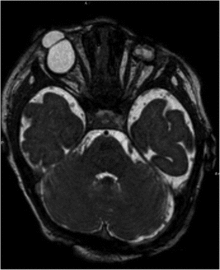

| Bilateral cryptophthalmos with microphthalmos in the left ocular globe and abnormal right ocular globe in a female infant with Fraser syndrome. | |

It is characterized by developmental defects including cryptophthalmos (where the eyelids fail to separate in each eye), and intersex development in the genitals (such as micropenis or clitoromegaly) and cryptorchidism.[3] Congenital malformations of the nose, ears, larynx and renal system, as well as developmental delays, manifest occasionally.[4] Syndactyly (fused fingers or toes) has also been noted.[5]